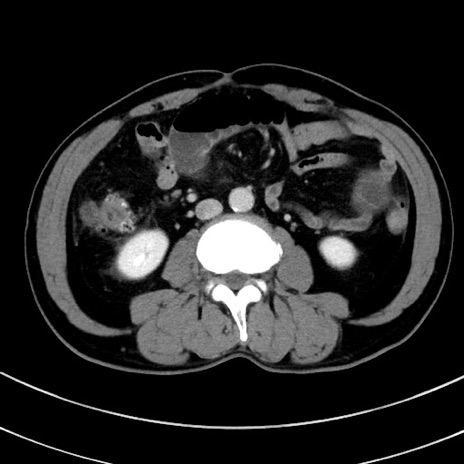

冠状断像

症例8(横断像)

【症例】 60歳代男性

【主訴】 黒色吐物

【現病歴】 4日前から嘔気自覚、2日前の朝食後にも嘔気あり、自分で手で嘔吐反射起こし嘔吐したところ血が混ざっていたため受診。

【既往歴】 5年前汎発性腹膜炎を伴う急性虫垂炎で手術、高血圧、前立腺肥大症、高脂血症

【身体所見】 腹部正中に手術癩痕あり 腹部平坦・軟圧痛なし膨満感あり

【データ】WBC 8400、CRP 4.54